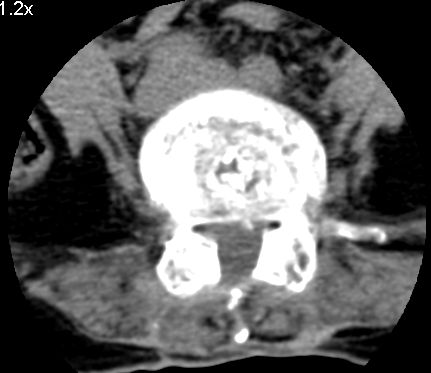

以下是引用余辉在2007-9-4 21:00:00的发言:[br]椎体棘突有点异常(像是被切割了),不知有否手术史,如椎体融合术等。单纯的退行性变可以出现椎间隙变窄,但同时一般会出现椎体上下缘的硬化增生,且椎体间完全融合的机率更小,本例椎体完全融合且椎体上下皮质缘破坏掉了,如果没有手术史,就应该考虑椎间盘炎性病变了,且椎体棘突及棘间韧带的变化也并不是不支持这个,多数小关节也融合了,且其形态也容易让人联想到如强脊炎及类风关等病变。[br][br][本贴已被 余辉 于 2007-9-4 21:03:55 修改过]

以下是引用chry3在2007-9-4 20:42:00的发言:[br]椎间盘病史?是什么样的病史,无双下肢放射痛,那就不是椎间盘突出了。是感染、什么性质的?[br]从图象看椎间隙消失,椎间盘组织未见,锥体滑脱是因为椎间盘溶解造成的[br]l4、5椎体骨质结构未见异常,l5上缘是l4的长期压迫所致[br]还是考虑椎间盘感染,结核。[br]